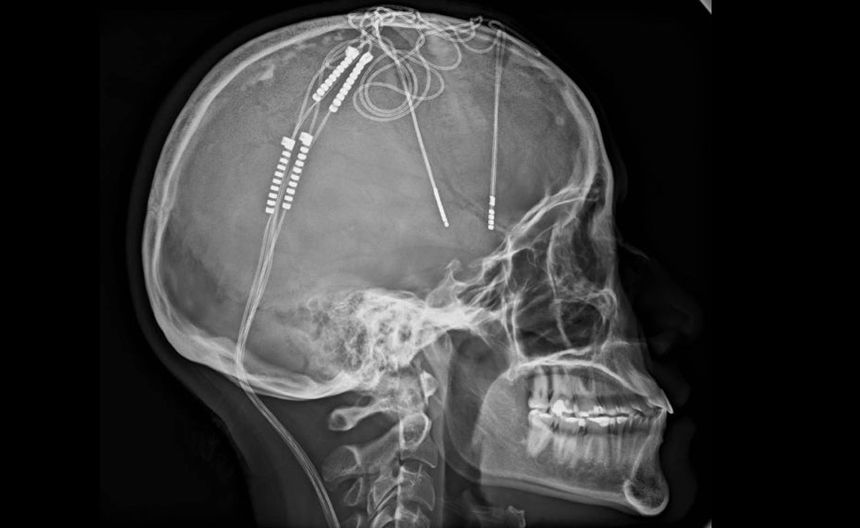

“Estuve seis horas despierta durante la cirugía. Superó toda la ficción. Sentía que mi mente estaba siendo reprogramada”, expuso. La operación, encabezada por el neurocirujano William Contreras, implicó la implantación de electrodos en su cerebro y una batería en el pecho que emite impulsos eléctricos para modular la actividad cerebral.